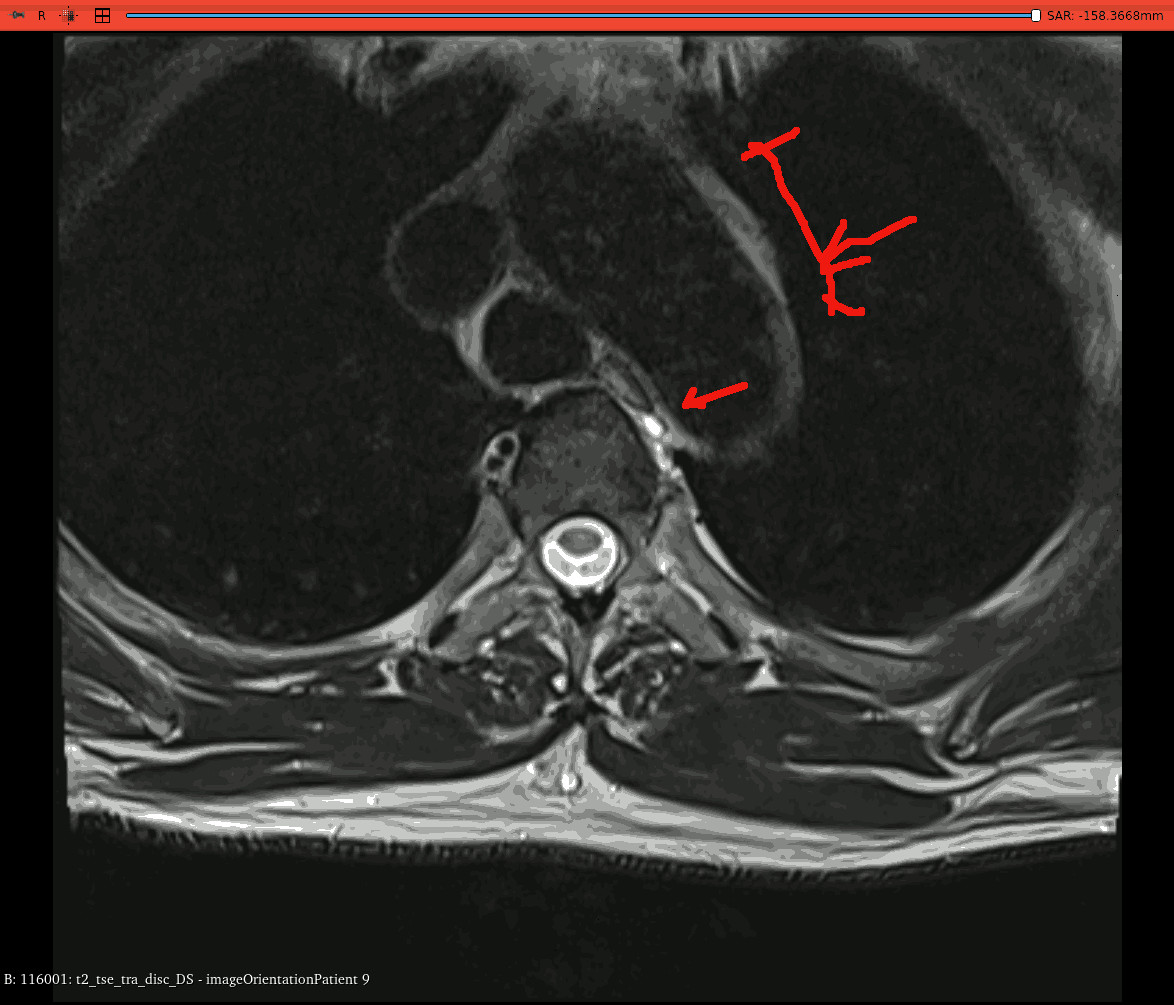

this 1.5 T MRI scan was taken initially to check for spine

anomalies (damaged discs were found). therefore it is not

entirely suited to finding pericarditis however the two anomalies

shown are very clear: a white thickening of the heart sac to

well beyond the normal 2mm thickness, and a white intensity

of approx 5mm in diameter.

it was pure luck to get these anomalies as the slices, being

a spine MRI, are a considerable distance apart - approx 6 cm.

additionally the weighting is not suitable for MRI detection of

pericarditis: special MRI scans are needed with codenames

such as "SSRI"